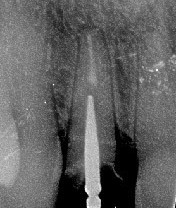

La racine de l'incisive centrale est fracturée. Le cliché 3D indique l'axe à respecter lors de l'implantation grâce au logiciel de simulation